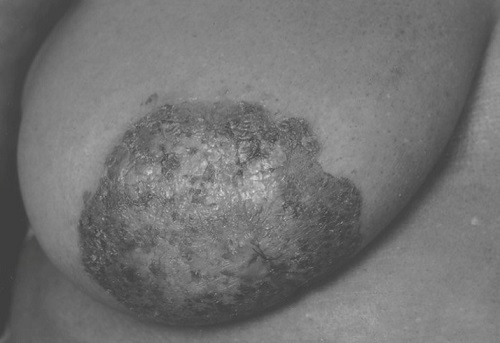

【112-1 醫學(五) 第18題】照片顯示之乳房病灶,最有可能為下列何種疾病?

這張圖顯示乳頭乳暈區域有濕疹樣、結痂、脫屑的病灶。看到乳頭乳暈的慢性濕疹樣變化,第一個要想到乳房柏哲氏病 (Paget's disease of the breast)。